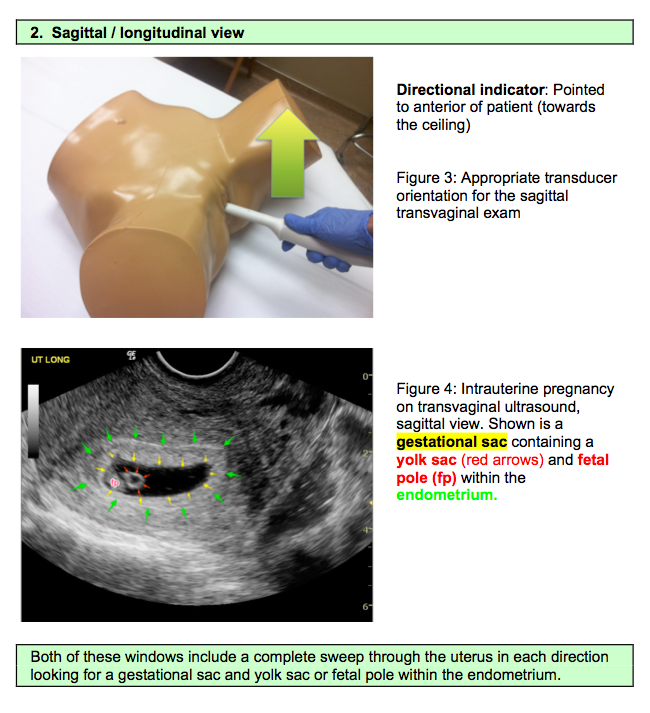

Ultrasound Leadership Academy: Ultrasound in Early Pregnancy — EM Curious

PV Card: Focused 1st Trimester Pregnancy Transvaginal Ultrasound